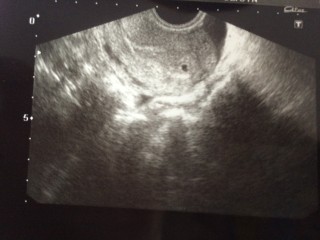

生理予定日から一週間の5w0d。 基礎体温もガタガタで腹痛もあったため早めに受診することに。 とても小さな6ミリの胎嚢が確認出来ました。 しかし先生からは出血してるねと言われ、物凄く不安になりました。 昨年流産していて、その日は朝にガクっと体温が下がったのでその事も先生に話すと流産止めのプロゲデポーという注射を打つことに。 その他にも止血剤や子宮の収縮を抑える薬を処方されました。 外に出血は無いものの生理痛のような鈍痛がずっとあり、5週目は気が気ではありませんでした。 しかも、胎嚢の形がいびつじゃないか? 細長すぎないか?と余計な心配ばかりしていました。